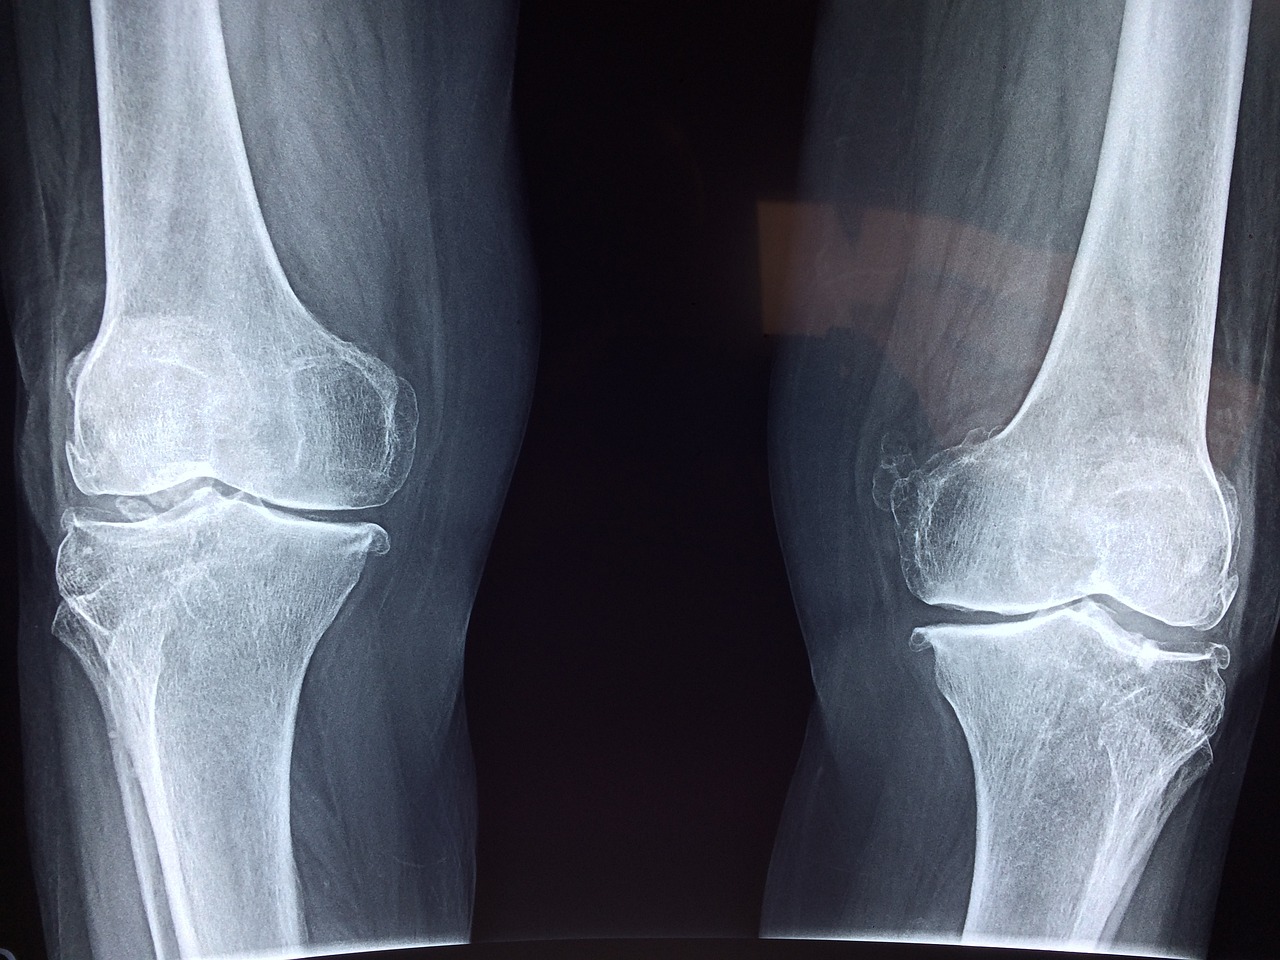

무릎 통증은 여러 가지 원인에 의해 발생할 수 있습니다. 가장 일반적인 원인은 관절염입니다. 퇴행성 관절염이나 류마티스 관절염은 무릎의 연골을 손상시켜 통증을 유발합니다. 이러한 질환은 나이가 들면서 발생할 확률이 높아지며 관절의 염증과 통증을 동반합니다.

두 번째는 만성 통증으로 장기간에 걸쳐 지속되는 통증입니다. 만성 통증은 관절엽이나 퇴행성 변화와 같은 질환에 의해 발생할 수 있으며 일상생활에 큰 영향을 미칠 수 있습니다.